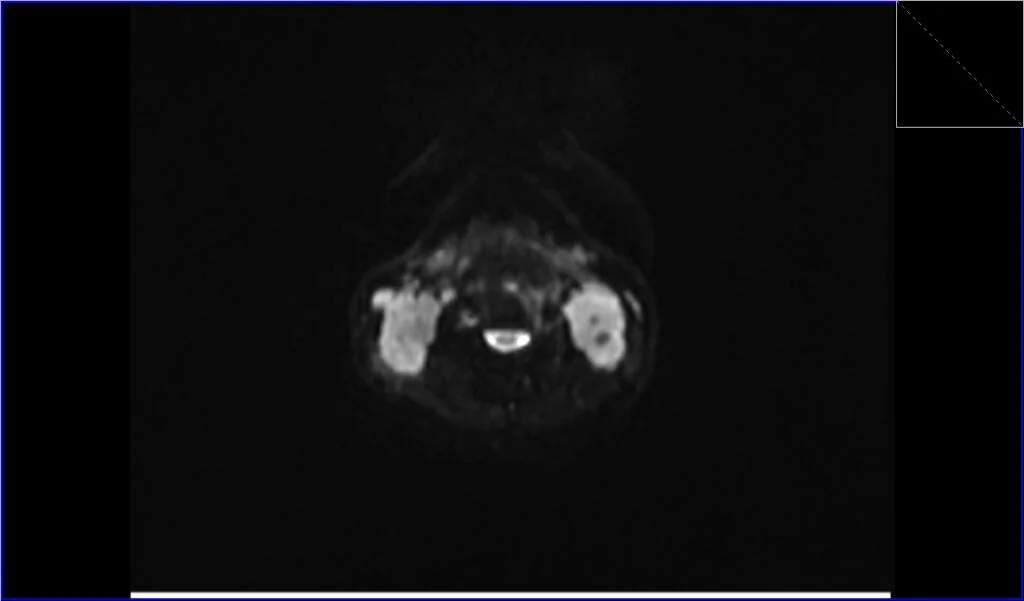

Diffusion-Weighted Imaging (DWI): DWI assesses the diffusion of water molecules within tissue. Lymphomatous tissue often restricts water diffusion due to high cellularity and increased nucleic content. On DWI, lymphoma can appear as areas of high signal intensity, and on the corresponding Apparent Diffusion Coefficient (ADC) maps, they will show low signal intensity, indicating restricted diffusion. This can help differentiate lymphoma from other neck masses.

ADC axial image shows Lymphoma